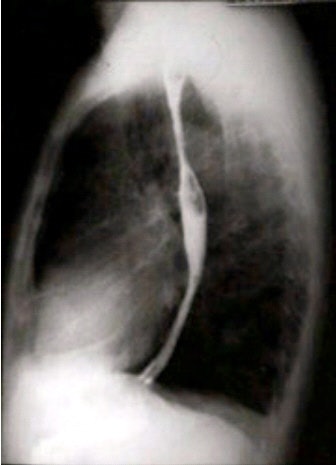

![]() |

| Lateral esophagus, single-contrast study. Image courtesy of Dr. Naveed Ahmad. |